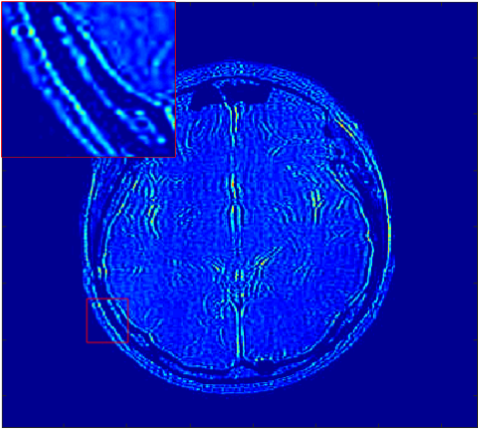

Where x is denoted as the MRI to be reconstructed, y are the k-space data, and Fusubscript𝐹𝑢{F_{u}} represents the under-sampled Fourier encoding matrix. The first term Fuxy22superscriptsubscriptnormsubscript𝐹𝑢xy22{\|{F_{u}}\emph{x}-\emph{y}\|}_{2}^{2} indicates data fidelity that can ensure the consistence between the Fourier coefficients of the reconstructed image and measured data. The second term Risubscript𝑅𝑖{R_{i}} is an analytical, sparsifying transform term, and αisubscript𝛼𝑖{\alpha_{i}} is a factor for balancing data fidelity and transform terms. MR images can be generated by inverse Fourier transform of the sampled k-space data, which are the Fourier coefficient of an object. However, aliasing artifacts (noise-like) are produced by the incoherence of under-sampled k-space in transform domain, as shown in Fig. 1.

Figure 1: The zero-filled reconstruction. (a) is a full-sampled MRI, (b) is a 20% radial sampling mask, (c) is the zero-filled reconstruction under (b), and (d) is the reconstruction using our method. Note that aliasing artifacts are clearly seen in the zero-filled reconstruction (c), which impair diagnostic information. However, our algorithm can remove these unpleasant artifacts (d).